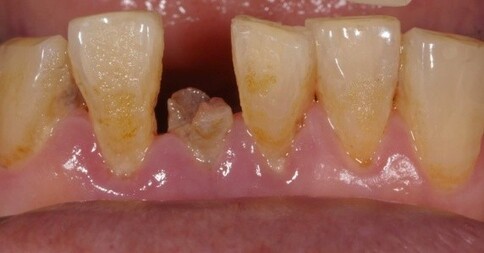

當您只有「單顆」門牙受損時,挑戰在於模仿隔壁那顆「天生的牙」。我們利用全瓷冠的高透光性創造視覺平衡,避免做出一顆看起來很新卻很突兀的假牙。

Case 4:技師比色驗證,達成理想結果。